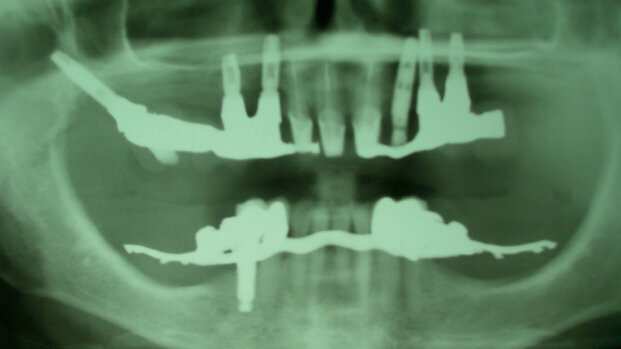

La paziente B.M. si rivolge, nell’anno 2002, alle cure di un odontoiatra in una città della Lombardia, per cui viene proposto e concordato un piano riabilitativo complesso consistente nell’inserimento di elementi implantari all’arcata superiore, specificatamente in posizione 13-14, 23-24 e 18 (Tuber mascellare, denominato anche impianto-pterigoideo), seguito da riabilitazione protesica fissa. Un altro impianto posizionato in sede 28 viene successivamente rimosso perché fallito. La situazione chirurgica definitiva risulta nella RX OPT mostrata nella Fig. 1.

Nella perizia del Consulente di Parte del 2003 (CTP iniziale, diverso dallo scrivente) si legge infatti: «All’esame ortopantomografico si nota: n. 3 pianti di destra di cui quelli in zona 13 e 14 scarsamente osteointegrati e presentanti una preoccupante invasione del cavo sinusale di destra (peraltro con note evidenti di opacità). A sinistra la presenza di n. 2 impianti endossei scarsamente osteointegrati e abbondantemente coinvolgenti la cavità sinusale di sinistra che presenta opacità diffusa».